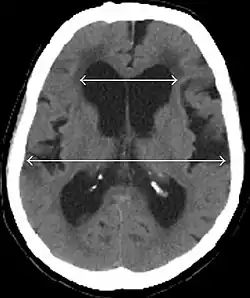

- Imaging from magnetic resonance imaging (MRI) or computed tomography (CT) is needed to demonstrate enlarged ventricles and no macroscopic obstruction to cerebrospinal fluid flow. Imaging should show an enlargement to at least one of the temporal horns of lateral ventricles, and impingement against the falx cerebri resulting in a callosal angle ≤ 90° on the coronal view, showing evidence of altered brain water content, or normal active flow (which is referred to as "flow void") at the cerebral aqueduct and fourth ventricle.

MRI scans are the preferred imaging. The distinction between normal and enlarged ventricular size by cerebral atrophy is difficult to ascertain. Up to 80% of cases are unrecognized and untreated due to difficulty of diagnosis.[22] Imaging should also reveal the absence of any cerebral mass lesions or any signs of obstructions. Although all patients with NPH have enlarged ventricles, not all elderly patients with enlarged ventricles have primary NPH. Cerebral atrophy can cause enlarged ventricles, as well, and is referred to as hydrocephalus ex vacuo. For these reasons it's utmost important to note that Evan's index although commonly used in imaging is not very specific for NPH. One recent systematic review and meta-analysis suggests that callosal angle has high diagnostic performance and is commonly used together with Evan's index.[23]